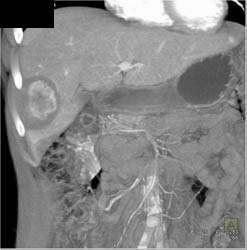

Hepatic Adenoma